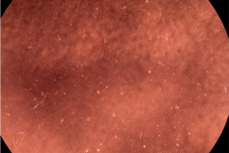

| Sample | Micrographs | ||

|---|---|---|---|

| 24 h | 48 h | ||

| Control |  |  | |

| F127 | 10 µg/mL |  |  |

| 50 µg/mL |  |  | |

| 100 µg/mL |  |  | |

| 200 µg/mL |  |  | |

| F127/PA = 10/1 (g/g) | 10 µg/mL |  |  |

| 50 µg/mL |  |  | |

| 100 µg/mL |  |  | |

| 200 µg/mL |  |  | |